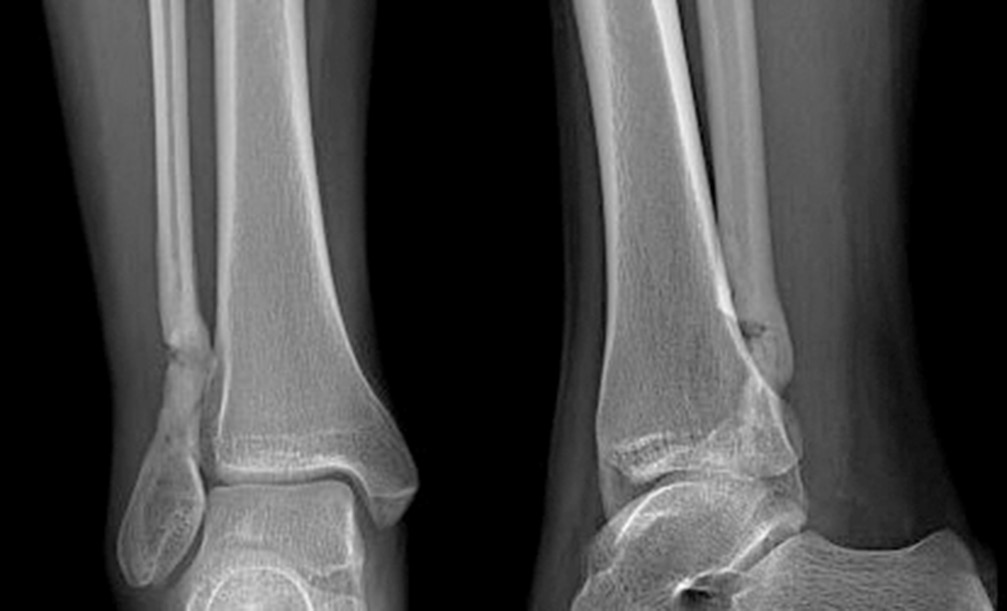

11.04.2017 из-за неэффективности консервативного и оперативного лечения проведена субпериостальная сегментарная резекция склерозированного участка нижней трети правой малоберцовой кости в пределах неизмененной костной ткани. Размеры резецированного участка кости составили 1,5 × 3,0 см. По гистологическим данным определен участок остеосклероза. Наложена гипсовая лонгета сроком на 8 нед. (рис. 5).

Рис. 5. Рентгенограмма. Состояние через месяц после операции — сегментарной резекции склеротически измененного участка нижней трети малоберцовой кости

В послеоперационном периоде выраженность болевого синдрома снизилась (до 4–6 баллов по ВАШ). Проводили интенсивные реабилитационные мероприятия. Спустя 4 мес. после резекции склерозированного участка нижней трети малоберцовой кости на контрольной рентгенограмме определялись неоднородность структуры и нечеткость контуров дистального метадиафиза малоберцовой кости с формированием костной мозоли (рис. 6). Признана целесообразной полная нагрузка на конечность. При осмотре через 6 мес. после операции болевой синдром отсутствовал (по ВАШ 0 баллов), наблюдалась потеря чувствительности в области тыльной поверхности стопы. Последующее обследование через 12 мес. после резекции показало отсутствие болевого синдрома и других клинических проявлений. По данным компьютерной томографии прослеживалась отчетливая тенденция к восстановлению органотипической костной структуры нижней трети малоберцовой кости в зоне оперативного вмешательства (рис. 7).

Рис. 6. Рентгенограмма спустя 4 мес. после операции (сегментарной резекции). Образование костной мозоли, заполнение дефекта кости новообразованной костной тканью

Рис. 7. Мультиспиральная компьютерная томография спустя 12 мес. после операции — сегментарной резекции нижней трети малоберцовой кости. Определяются признаки наметившейся дифференциации костной структуры на кортикальный слой и костномозговую полость